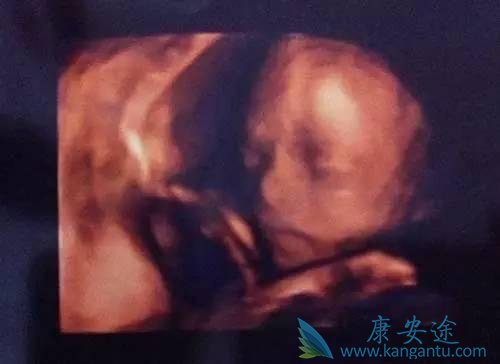

第四次B超检查—18-24周

这是整个孕期最全面的一次超声检查,它还有一个孕妈们最熟悉的名称——“大排畸”检查。为了提高病变检出率,医院基本都是采用清晰度更高的三维或四维彩超进行系统超声检查。此次检查最重要目的是观察胎儿全身各系统结构是否存在畸形,主要包括颅内结构、颜面、心脏、胃泡、肾脏、膀胱、脊柱、四肢等,如果条件良好,还能够建立宝宝的面部三维图像。

准妈妈们可以看到肚子里宝宝的容貌,甚至宝宝的动作和表情!大部分的胎儿畸形可在此时期被排查,但是一些小的畸形,如手指、脚趾这些小的病变很难查出来,还有一些先天异常是发展性的,到怀孕后期才出现。此外,超声也不是万能的,观察还会受胎儿体位、孕妇腹壁肥胖、羊水过多过少等条件限制无法清晰显示胎儿,所以“大排畸”依然无法百分之百排除所有的先天性疾病,这就更体现了规范的按照医生安排进行B超检查的重要性了。